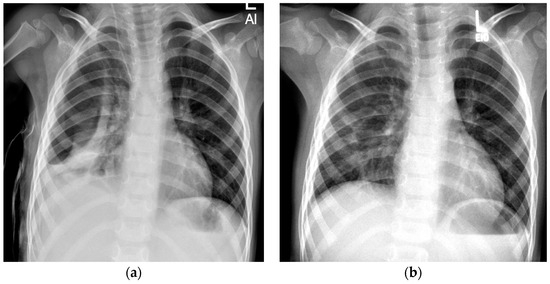

During our inpatient treatment, a pneumothorax was detected in 20 out of 47 patients (43%). Pneumothorax was still detectable in 11 patients at the time of their discharge from inpatient treatment. At the end of our FU, a spontaneous resorption of the pneumothorax was observed in eight patients (Figure 2). In three patients, a pneumothorax ex vacuo remained identifiable. The course of treatment is shown below (Figure 3).

Figure 2. Spontaneous resorption of a pneumothorax in a 3-year-old boy. (a) Anterior–posterior (AP) chest radiograph taken at the time of discharge reveals a right-sided pneumothorax. (b) Spontaneous resorption of the pneumothorax at 2-month follow-up.